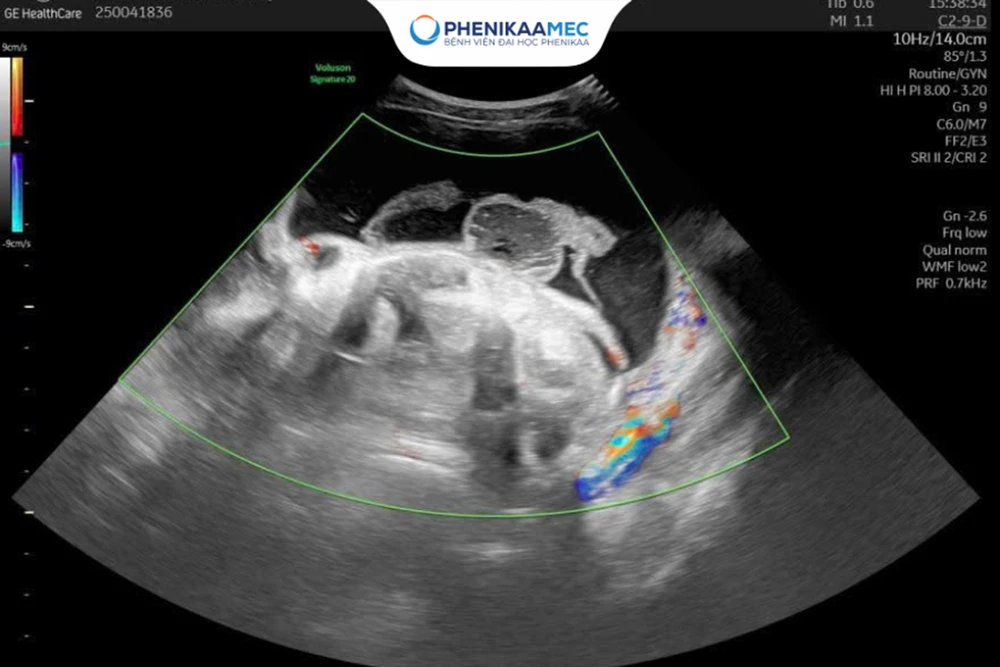

u-nang-buong-trung-co-nguy-hiem-khong-truong-hop-nao-can-mo-ngay.png

Khối u kích thước lớn gây chèn ép các cơ quan.